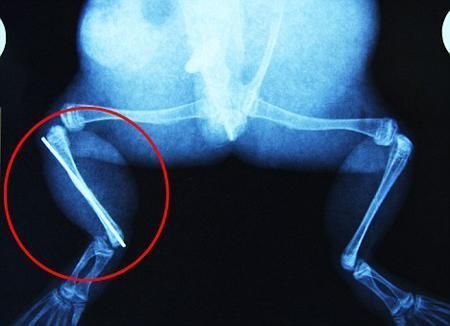

布魯萊的主人,居住在南非約翰內(nèi)斯堡附近的62歲的安妮·米恩斯說:“我對這只青蛙如此關(guān)心,人們一定認(rèn)為我瘋了,但是我無法眼睜睜看著它那么痛苦。青蛙因其靈活的腿腳而著稱,一想到布魯萊的腿里要留下一個薄金屬片,我就感到心痛。然而我知道,如果不進(jìn)行手術(shù),布魯萊以后就沒辦法動彈了。因此我匆匆趕到獸醫(yī)那里,央求他給這只可憐的青蛙動手術(shù)。這位獸醫(yī)整天救助小貓小狗,他很難理解為什么我這么擔(dān)心一只青蛙,但是最終他還是答應(yīng)了給布魯萊做手術(shù)。手術(shù)后是幾個小時的焦急等待,我們希望它能快快蘇醒過來。不過現(xiàn)在它的傷口已經(jīng)愈合,又能在花園里跳來跳去了。X光照射顯示,它會恢復(fù)的跟以前一樣。”

野生生物專家安妮經(jīng)常為學(xué)校寫教材,她認(rèn)為這是人類第一次通過手術(shù)給一只青蛙接斷腿。在手術(shù)開始階段,獸醫(yī)把少量給狗用的麻醉藥注入到這只青蛙體內(nèi),讓它失去知覺。然后他在布魯萊的斷腿上切開一個小口,把一根小鋼針植入腿里。最后獸醫(yī)給它縫了9針,把切口縫合在一起。僅僅幾周后,布魯萊就能在安妮家附近活動了。這只青蛙大約已有25歲,主要以嚙齒動物、蛇和其他青蛙為食。布魯萊所屬的牛蛙種群正在不斷減小,目前只能在非洲南部的濕地里才能看到這種青蛙。

安妮有2個孩子,她已經(jīng)從事20多年兩棲動物保護(hù)工作。她認(rèn)為鄰居家的狗狗在把布魯萊從地下刨出來的時候,它正在地下冬眠、她說:“世界上只有這個地區(qū)能看到這種牛蛙,這種青蛙現(xiàn)在變得越來越稀少。因?yàn)槲覐氖乱吧锉Wo(hù)工作,因此認(rèn)識很多兩棲動物專家,但是以前他們誰也沒見過這種事情?吹讲剪斎R越來越健康我非常開心。現(xiàn)在還需要一段時間,它的金屬腿和它的骨骼才能融為一體,那時布魯萊會跟以前一樣健康。我們認(rèn)為這個過程需要幾周時間,但是一旦它完全康復(fù),我希望把它放歸大自然,讓它重新回到它最鐘愛的濕地里。”